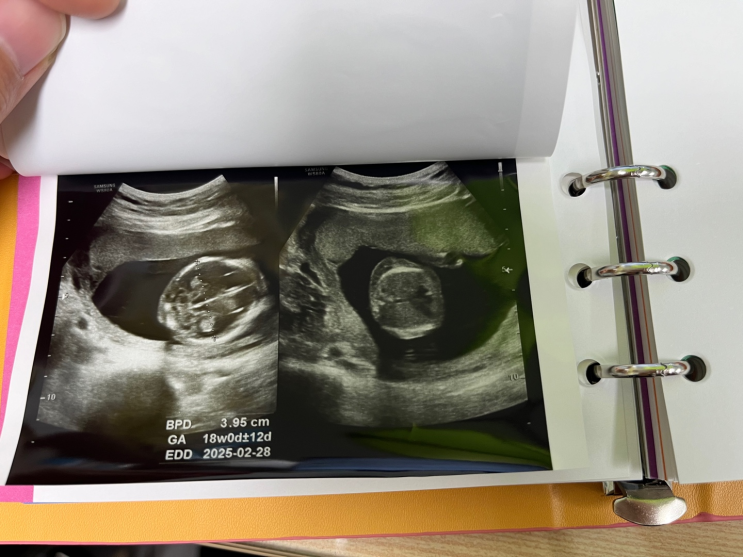

[임신일기] 16주3일 정기검사 (2차 기형아 검사)

성별을 알 수 있는 16주가 왔다. 남편이 전부터 아들 같다고 초음파만 봐도 잘생겼다 했는데 나는 딸이면 ...

[임신일기] 다운증후군 고위험(1:260), 니프티 검사 (17주3일) +현대해상 보험금 청구

원장님 전화를 받았는데 다운증후군 고위험 1:260 이라고 하셨다. 내 나이 평균으론 1:513 이 저위험 수치...